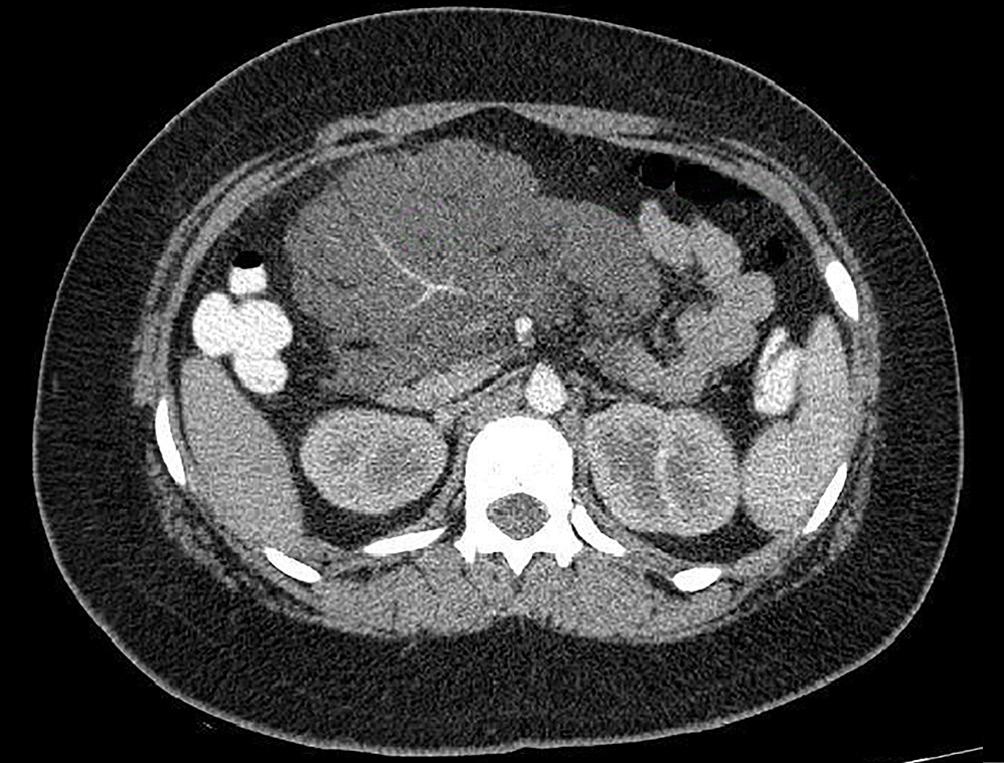

La endoscopía superior es un procedimiento fundamental para el diagnóstico, la evaluación de la respuesta al tratamiento y el monitoreo a largo plazo de la actividad de la EEo. Los hallazgos endoscópicos típicos incluyen edema (reducción de vascularidad), anillos esofágicos fijos, exudados blancos, surcos longitudinales, estenosis, estrechamiento de la luz esofágica, friabilidad de la mucosa (mucosa en papel crepé) y una consistencia firme de la mucosa al realizar biopsias (signo de “tracción" o "resistencia”) en pacientes con fibrosis (Figura 1). Estos hallazgos no son patognomónicos y no constituyen un criterio diagnóstico; sin embargo, cuando se evalúa de forma cuidadosa, en la gran mayoría de los casos se pueden observar.19-21

En el panel A se observa un esófago con edema difuso y pliegues longitudinales; en el panel B se aprecia edema con pliegues y exudados blanquecinos; en el panel C se evidencia un estrechamiento luminal acompañado de anillos esofágicos y exudados; y en el panel D se muestra un desgarro mucoso posterior a la dilatación con bujía de Savary, hallazgo esperado tras este procedimiento terapéutico.

Figura 1. Características endoscópicas de la esofagitis eosinofílica